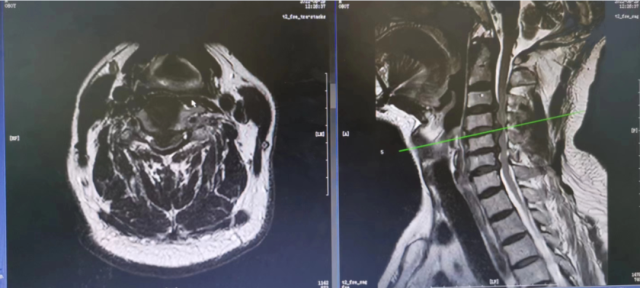

前不久,一名80 岁的男性患者,以“颈部疼痛伴双手麻木,双下肢无力1月余”为主诉入我院脊柱外科。

门诊查MRI显示:颈椎多节段椎间盘突出,椎管重度狭窄,脊髓受压严重,须行手术解除神经压迫。

考虑到患者年龄大合并高血压、冠心病、腔隙性脑梗死多种并发症,围手术期并发症高,同时,患者颈椎脊髓受压严重,手术风险大,难度高,脊柱外科先是与麻醉科、心血管内科、神经内科及重症医学科进行了多学科会诊。

随后,在张积利主任的带领下,与科室成员反复讨论,最终,为患者制定了“后路椎板切除+椎管扩大减压术”的治疗方案,以最小手术创伤,以最短的手术时间完成“神经减压”。

7月6日张华峰博士带领科室的医生顺利完成“后路椎板切除+椎管扩大减压术”

术前磁共振

术后MRI显示脊髓压迫完全解除